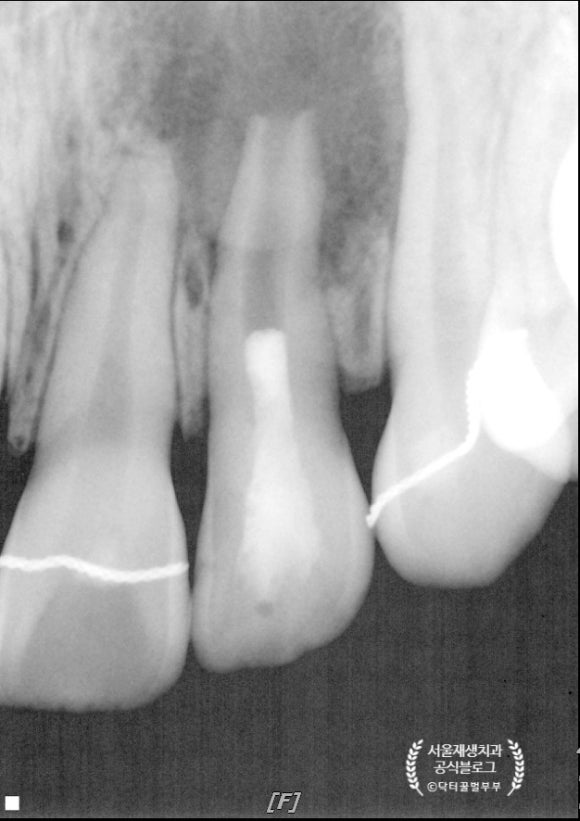

치료 후 7 개워이 지났습니다.

치아 뿌리는 더욱 두꺼워졌고, 병소도 거의 다 사라졌습니다.

이제 시간이 더 지나면 뿌리는 더욱 성숙해질테고, 병소였던 부위도 보다 밀도가 높은 뼈로 재생될테지요^^

치료 후 1년입니다.

이젠 차이가 보이시죠?

인접 치아들의 성장 속도를 따라가려면 아직 멀었지만,

뒤늦게 건강을 회복하여 스스로 재생되고 있습니다.

기특합니다^^